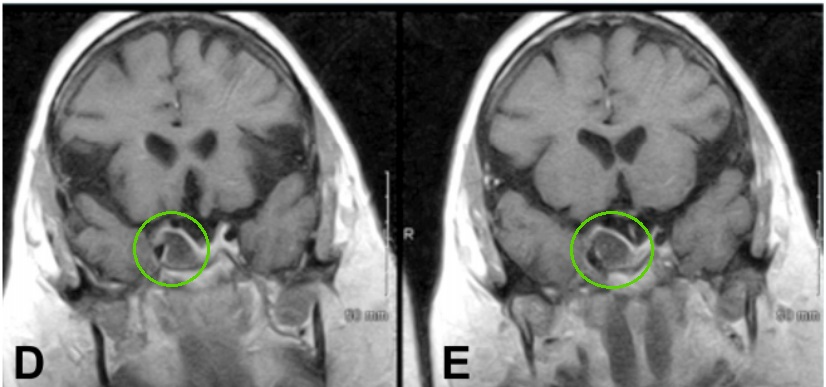

53岁男性患者,7年前在外院手术切除2级脑膜瘤。因出现三叉神经V1、V2区麻木,V3感觉迟钝入院。MRI见巨大脑膜瘤复发侵犯右侧海绵窦、眶顶、SphS、PPF和ITF并通过Meckel’s腔(MC)延伸至小脑桥脑角(CPA)(图 a-c)。

采用原额颞入路,显微镜+神经内镜-“双镜联合”,术后MRI显示肿瘤全切除。

术前术后影像对比:(A)术前MRI显示脑膜瘤延伸至后颅窝(PF)、海绵窦(CS)、眼眶和蝶窦(SS)。(B)肿瘤延伸至中窝、翼腭窝(PPF)和颞下窝(ITF)。(C)术前CT显示更大的蝶翼侵蚀和SS受累。(D, E)术后MRI显示肿瘤完全切除。(F)术后轴位CT扫描显示用于闭合的脂肪移植物。